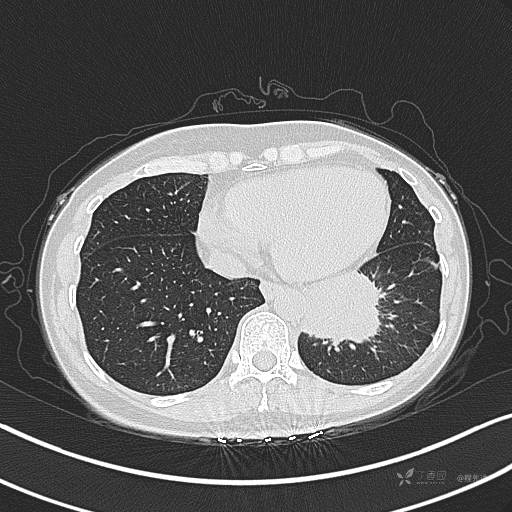

CT平扫

肺窗